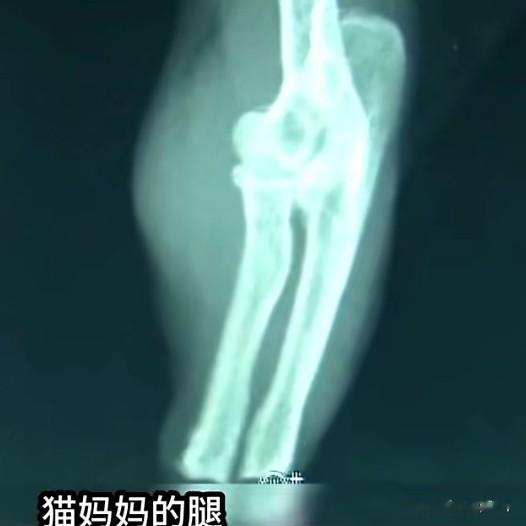

送医检查后,四只小猫各个健康壮实,可猫妈妈的检查结果却让所有人揪心。

兽医说:它的断骨切口光滑平整,是被人故意砍断的,难以想象它承受了何等剧痛,还挺着孕肚,忍着伤痛,硬生生把幼崽照料的这般周全,这就是母性撑起的奇迹。谁不为之动容呢?